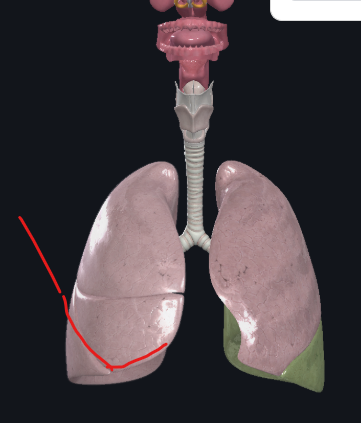

What structure is this?

Diaphragm

What structure is this?

Horizontal fissure of right lung

Oblique fissure of right lung

What structure is this?